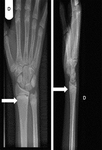

Punho direito de um paciente com raquitismo por deficiência de vitamina D antes do tratamento. Sua radiografia do punho direito revelou placas finais escleróticas e aumentadas do rádio e ulna (setas)

Seerat I, Greenberg M. Hypocalcaemic fit in an adolescent boy with undiagnosed rickets. BMJ Case Reports 2010; doi:10.1136/bcr.10.1136/bcr10.2008.1153